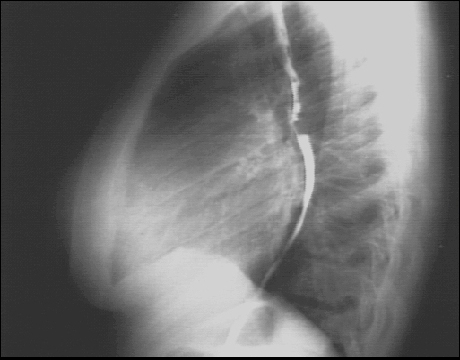

Chest X Ray

Labs - X Rays

PA and Lateral

Click on the xrays to enlarge them.

Choose the best interpretation of the chest X rays:

Left atrial enlargement and right ventricular enlargement

Left ventricular enlargement and pulmonary congestion

Calcified mitral annulus

Left ventricular enlargement and dilated aorta

Left ventricular enlargement and left atrial enlargement